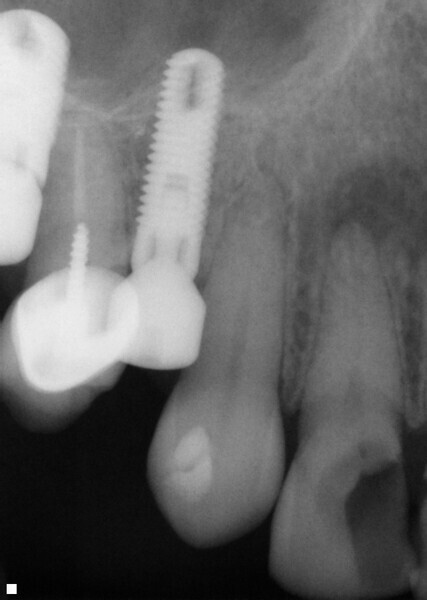

Fig. 14: Patient presented with complaint of pain on chewing on teeth 14 and 15 with increasing sensitivity to hot.

Fig. 15: Instrumentation performed with ExactTaperH DC files and obturation with a single cone of GP and Bioceramic Root Canal sealer completing endodontic treatment.